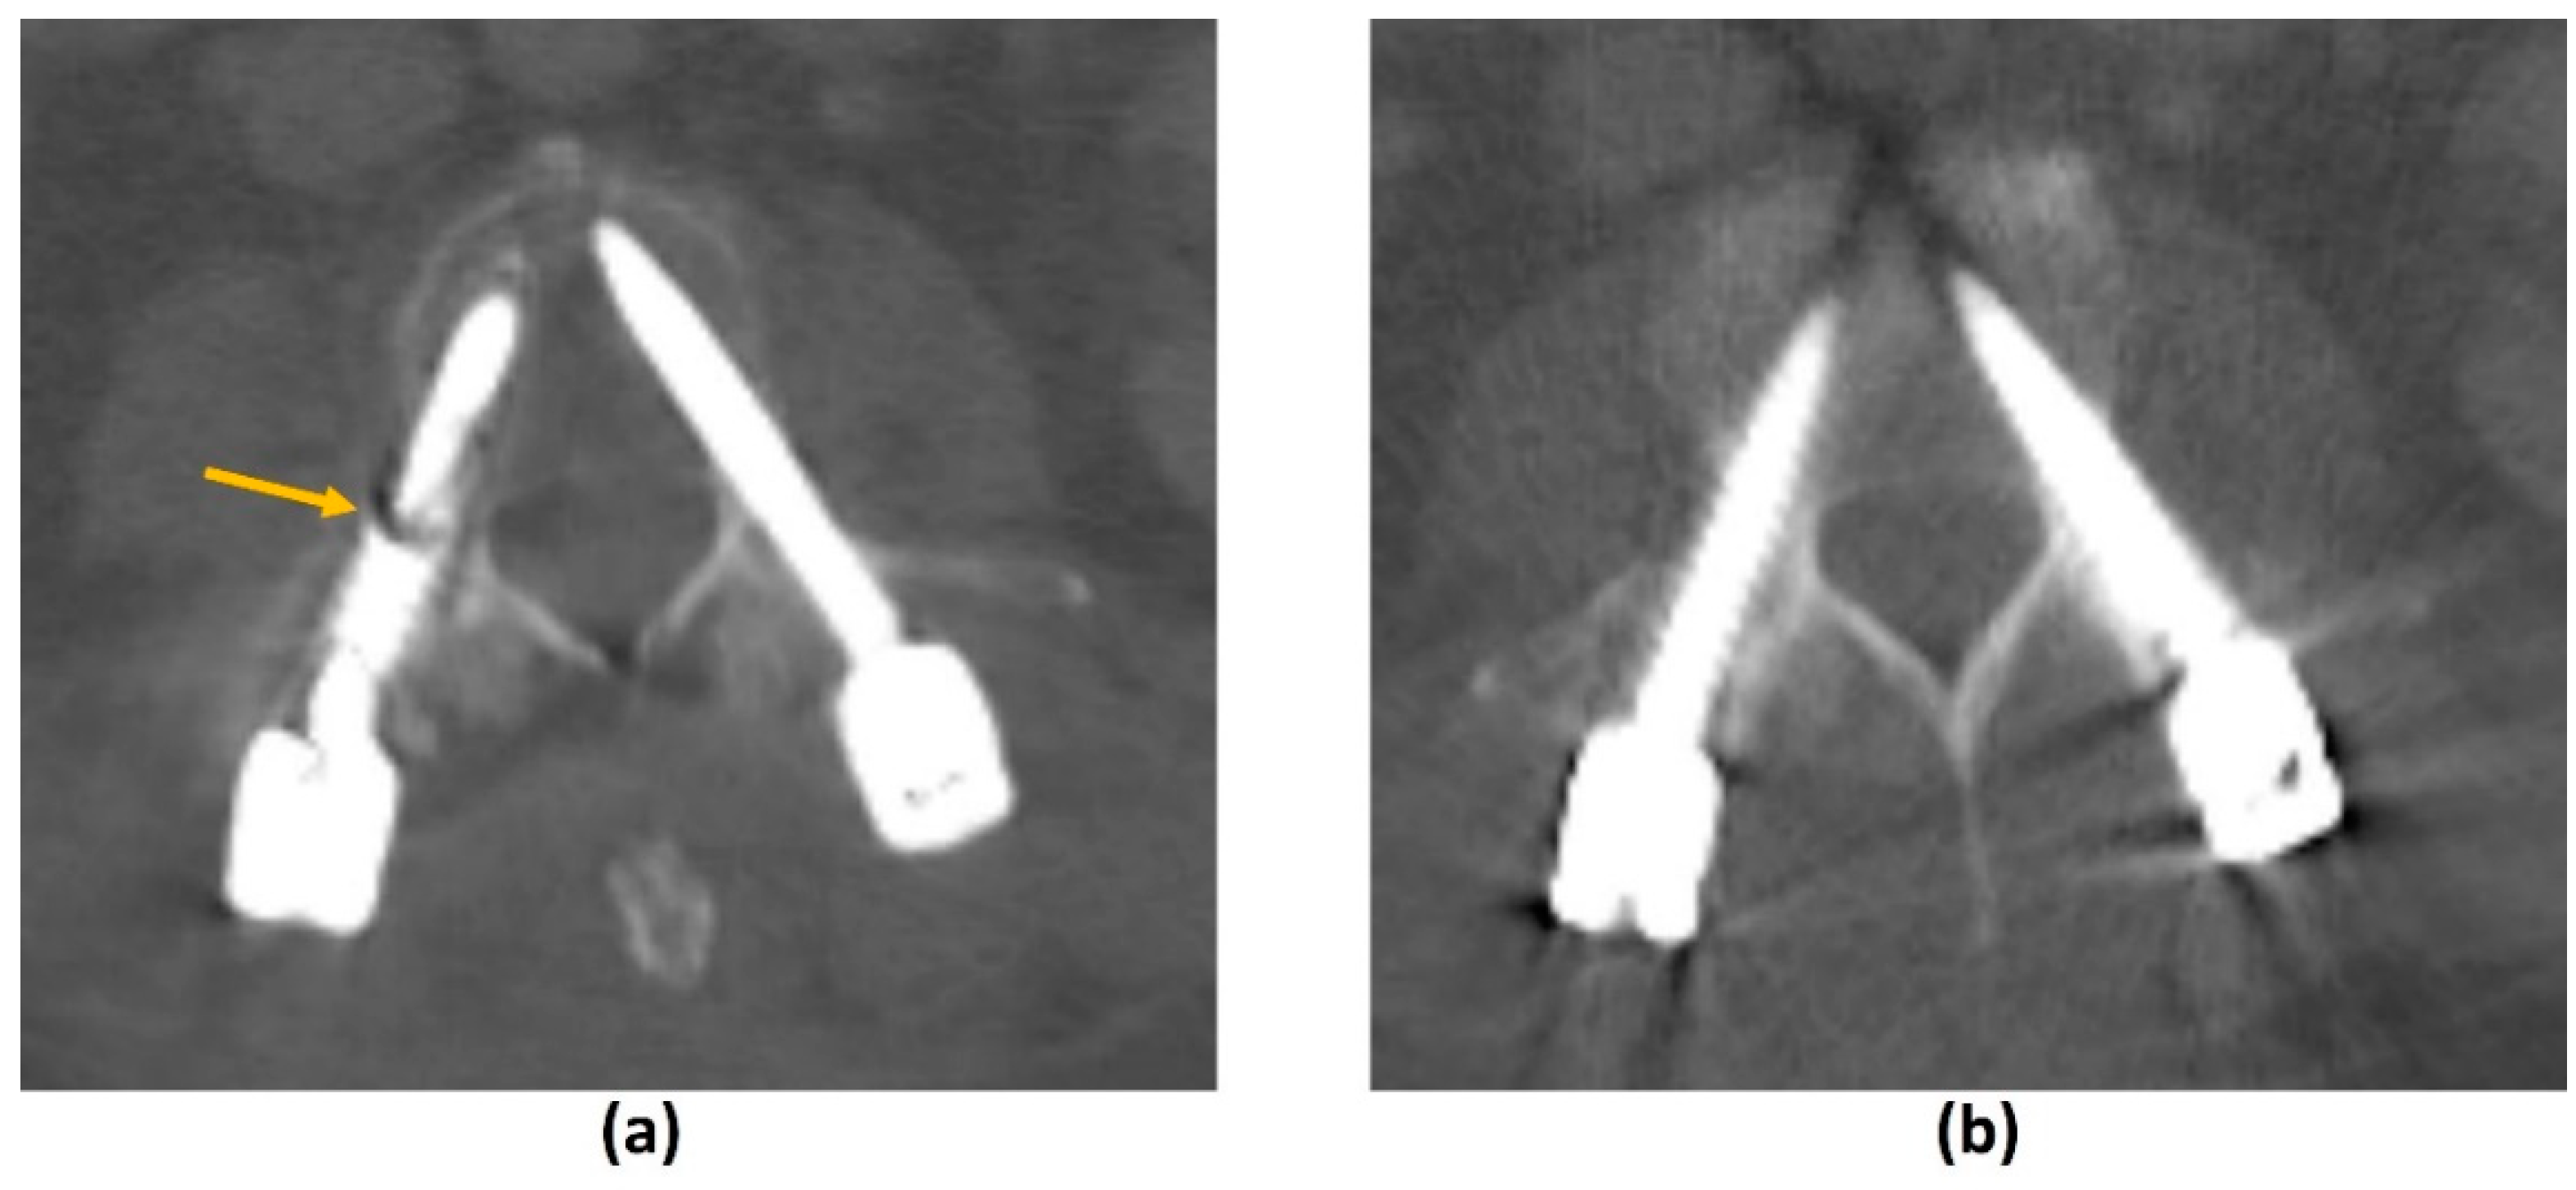

- Krätzig, T.; Mende, K.C.; Mohme, M.; Kniep, H.; Dreimann, M.; Stangenberg, M.; Westphal, M.; Gauer, T.; Eicker, S.O. Carbon fiber-reinforced PEEK versus titanium implants: An in vitro comparison of susceptibility artifacts in CT and MR imaging. Neurosurg. Rev. 2021, 44, 2163–2170. [Google Scholar] [CrossRef]

- Kumar, N.; Lopez, K.G.; Alathur Ramakrishnan, S.; Hallinan, J.T.P.D.; Fuh, J.Y.H.; Pandita, N.; Madhu, S.; Kumar, A.; Benneker, L.M.; Vellayappan, B.A. Evolution of materials for implants in metastatic spine disease till date—Have we found an ideal material? Radiother Oncol. 2021, 163, 93–104. [Google Scholar] [CrossRef] [PubMed]

- Kumar, N.; Ramakrishnan, S.A.; Lopez, K.G.; Madhu, S.; Ramos, M.R.D.; Fuh, J.Y.H.; Hallinan, J.; Nolan, C.P.; Benneker, L.M.; Vellayappan, B.A. Can Polyether Ether Ketone Dethrone Titanium as the Choice Implant Material for Metastatic Spine Tumor Surgery? World Neurosurg. 2021, 148, 94–109. [Google Scholar] [CrossRef] [PubMed]

- Zimel, M.N.; Hwang, S.; Riedel, E.R.; Healey, J.H. Carbon fiber intramedullary nails reduce artifact in postoperative advanced imaging. Skelet. Radiol. 2015, 44, 1317–1325. [Google Scholar] [CrossRef]

- Osterhoff, G.; Huber, F.A.; Graf, L.C.; Erdlen, F.; Pape, H.C.; Sprengel, K.; Guggenberger, R. Comparison of metal artifact reduction techniques in magnetic resonance imaging of carbon-reinforced PEEK and titanium spinal implants. Acta Radiol. 2021, 2841851211029077. [Google Scholar] [CrossRef]